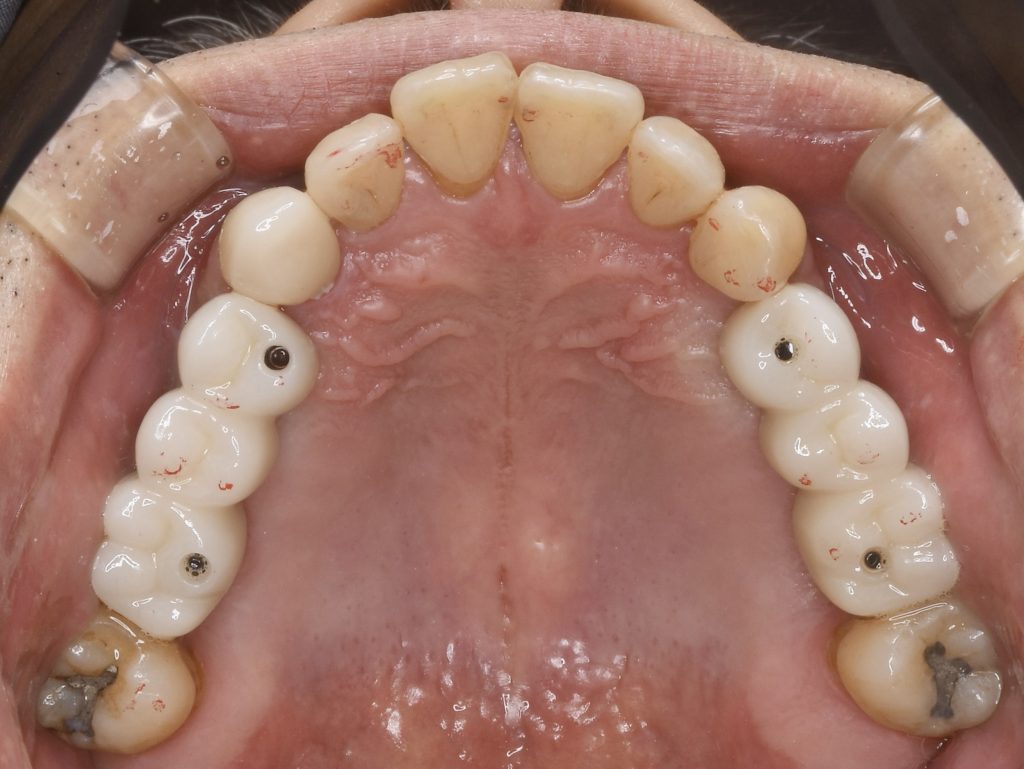

下記の症例は上顎臼歯部(上の奥歯)の骨量が不足している症例に対し、難易度の高いサイナスリフトを行い、骨量を改善させたのちインプラント埋入を行いました。

上記の症例にかかる費用 約430万円(税抜)